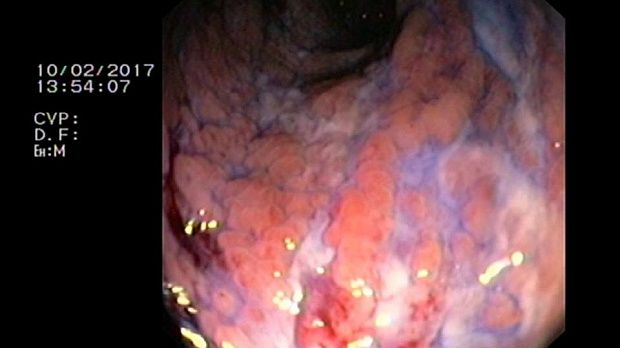

- Атлас

2 мл ( это мин сум, а мы делаем до 10 мл 3% перекись+200 мл физ раствора